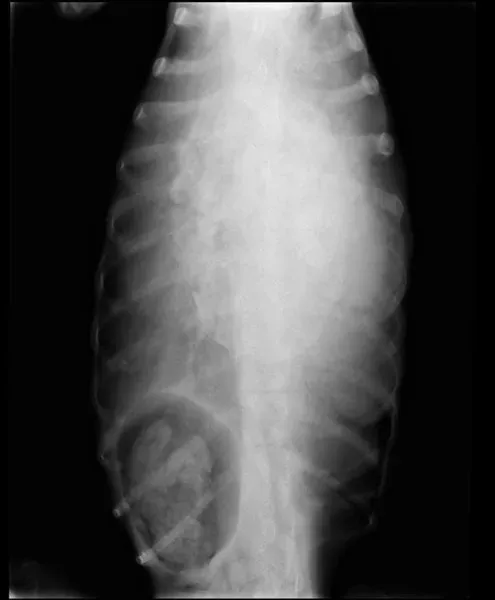

La Clinica è dotata di un proprio laboratorio di ematologia e biochimica, di un reparto di radiologia e di un ecografo.